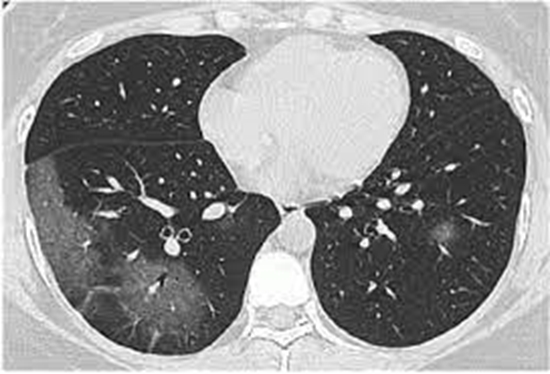

مقایسه یافته های سی تی اسکن قفسه سینه مربوط به برونکوپنومونی ایجاد شده توسط کرونا ویروس عامل 19 COVID در بیماران دیابتی ایجاد شدهی و غیر دیابتی مبتلا به 19 COVID بستری شده در مجتمع بیمارستانی امام خمینی تهران در اسفند 1398 و فروردین 1399

سی تی اسکن قفسه سینه مربوط به برونکوپنومونی ایجاد شده توسط کرونا